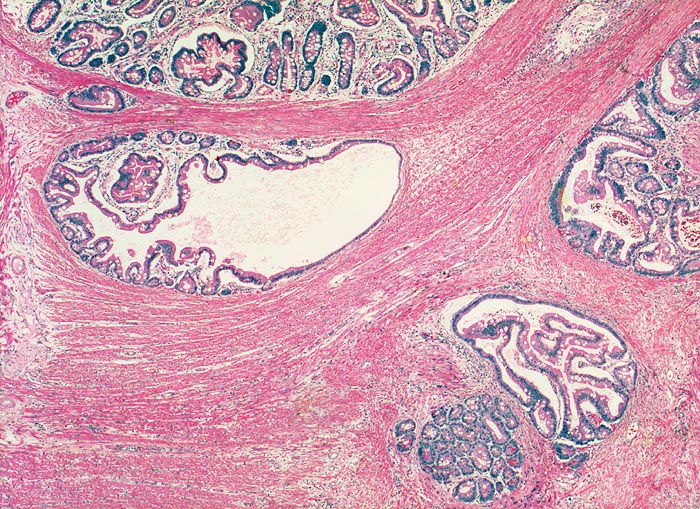

AP/ Peutz-Jeghers Polyp, Dünndarm

Peutz-Jeghers Polyp, Dünndarm

Jejunum